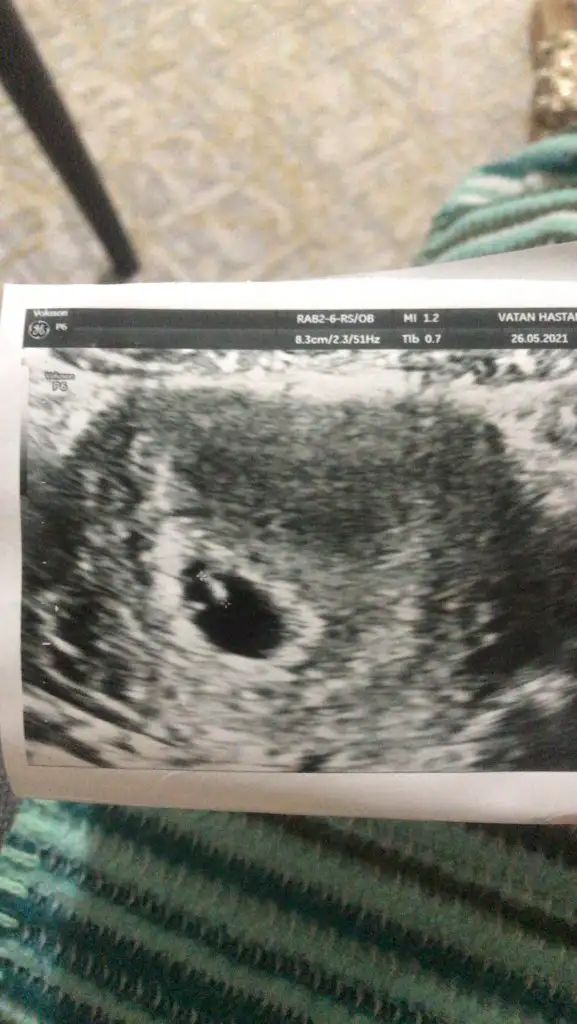

Bende karindan ultrasyon yorum yapabilirmissiniz

Eklentiler

• IMG-20210526-WA0004.webp

23,6 KB · Görüntüleme: 599